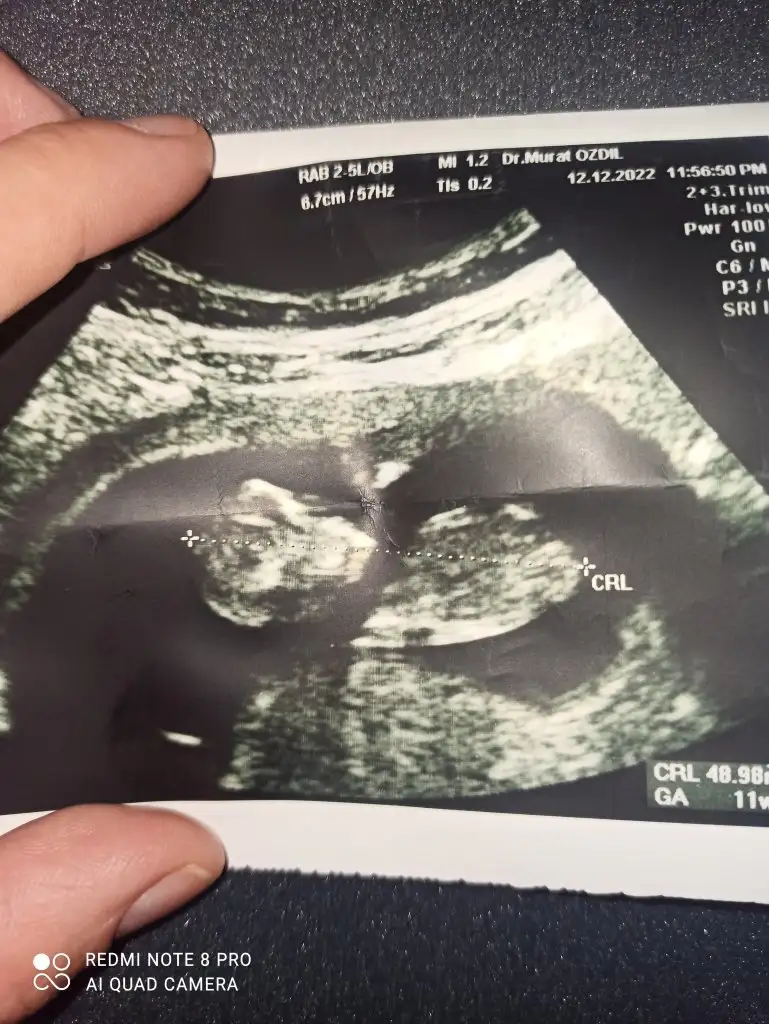

Amin canım cümlemizin sağlıklı sıhhatli olsun hayırlısıyla evlatlarımızı kulaklarımıza alalım. 12. Haftadayiz ama bebekler arasında 3 gün fark var buda çok önemli degil zamanla gelişimleri artiyormus. 12+1-12+4Maşallah canım ne güzel rabbim sağlıkla da kucağına almayı nasip etsin inş oğluşun ve kızınıbugün kaç haftalıktın öğrendiğinde?

Hamileliğiniz ilk nasıl hissettiniz ne gibi ağrı felan yaşadınız mı acabaAmin canım cümlemizin sağlıklı sıhhatli olsun hayırlısıyla evlatlarımızı kulaklarımıza alalım. 12. Haftadayiz ama bebekler arasında 3 gün fark var buda çok önemli degil zamanla gelişimleri artiyormus. 12+1-12+4

Amin canımAmin canım cümlemizin sağlıklı sıhhatli olsun hayırlısıyla evlatlarımızı kulaklarımıza alalım. 12. Haftadayiz ama bebekler arasında 3 gün fark var buda çok önemli degil zamanla gelişimleri artiyormus. 12+1-12+4